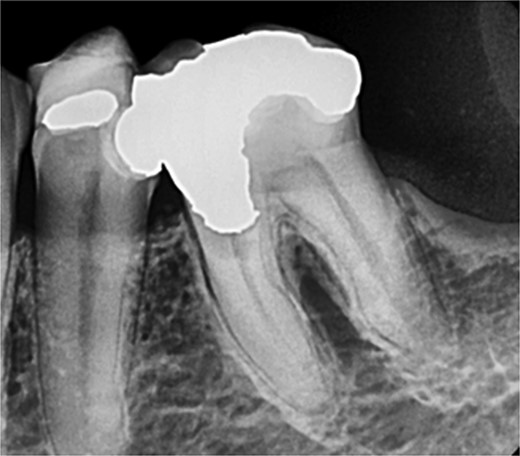

A 59-year-old male patient presented with a complaint of pain while biting on his lower left posterior teeth. Clinical examination revealed an extensive amalgam restoration on the lower left first molar (tooth 36) with a fractured restoration and secondary caries on the lingual aspect. The tooth was non-responsive to thermal testing and electrical pulp sensibility testing (EPT) and was tender to percussion. Radiographic examination showed radiolucency beneath the restoration on the mesial root surface, indicative of caries, along with furcation involvement and peri-radicular radiolucency. The tooth was diagnosed with pulpal necrosis and symptomatic apical periodontitis associated with extensive root caries (Fig. 6 and 7).

Periapical radiograph of tooth 36 shows large radiopacity, indicating a restoration on the crown extending to the mesial root surface. Radiolucency was detected beneath restoration on the mesial root surface, indicating caries. Peri-radicular radiolucency was observed in the furcation region.